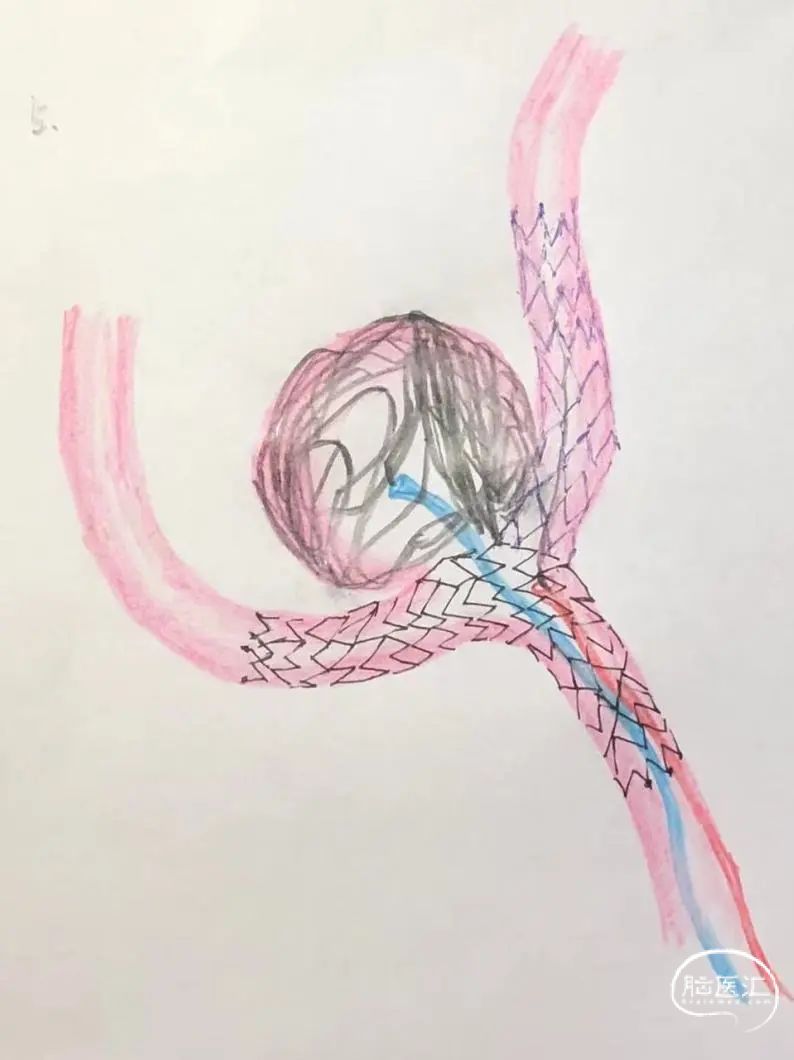

对侧支架锚定解袢过程示意图。

支架释放过程:固定支架推送导丝,回撤45°微导管,最终完成3.0mm*24mm Atlas支架的释放。

将3.0mm*21mm Atlas支架释放到同侧大脑前动脉A2段,近端衔接在第一个支架的体部,使两个支架形成T型结构,然后将弹簧圈解脱。